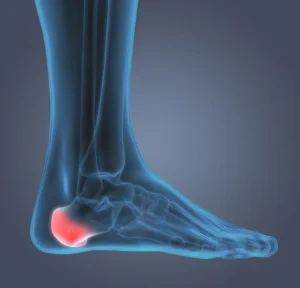

Debunking the Heel Spur Myth: What’s Really Causing Your Heel Pain Unless your healthcare provider has X-ray vision like Superman (complete with cape and outside underwear), they can’t diagnose a heel spur just by looking at your foot. Only an X-ray can confirm if a heel spur is present, and…

Women’s footwear and heel pain It’s no surprise-women’s feet face different challenges than men’s, particularly due to footwear choices. While this is a generalisation, men often wear more practical and comfortable shoes in the workplace, while women-especially in certain professions-may feel pressured to wear high heels or other unsupportive footwear.…